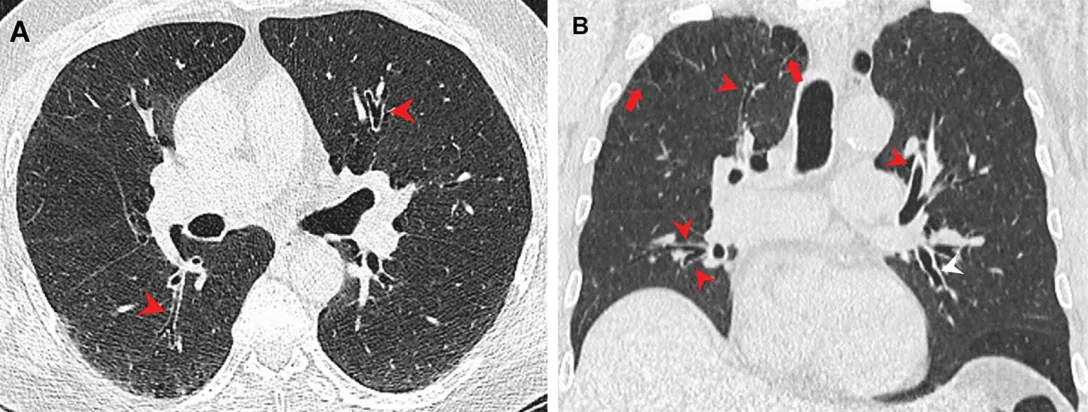

Исследование в журнале Radiology утверждает, что у курильщиков марихуаны чаще встречается эмфизема. Во время этого в легких увеличивается объем альвеол из-за разрушения перепонок между ними. При этом заболевании тяжело делать выдох. Кроме того, легкие становятся безжизненными. Ученые предполагают, что результаты исследования могли быть обусловлены тем, что дым марихуаны попадает в легкие нефильтрованным.

Ученые уже многое знают о влиянии сигарет на легкие, в отличие от марихуаны. Автор исследования Жизель Рева предположила, что курение "травки" накапливает в разы больше частиц в легких, чем обычная табачная сигарета. Чтобы проверить это утверждение, она и ее коллеги сравнили КТ 56 курильщиков марихуаны с результатами 57 некурящих, а также группой из 33 курильщиков табака.

Обнаружили, что три четверти или 75% курильщиков марихуаны получили эмфизему. Зато ценители табака получили более низкий результат – 67%.

КТ легких

Фото: Sci Tech Daily

Также ученые отмечают, что воспаление дыхательных путей было более распространенным именно у курильщиков марихуаны. Похожая ситуация была с гинекомастией – увеличение грудной железы у мужчин. Соотношение в процентах курильщиков табака и марихуаны было 11 к 38. Похожие результаты получили во время соответствующих по возрасту подгрупп тоже.